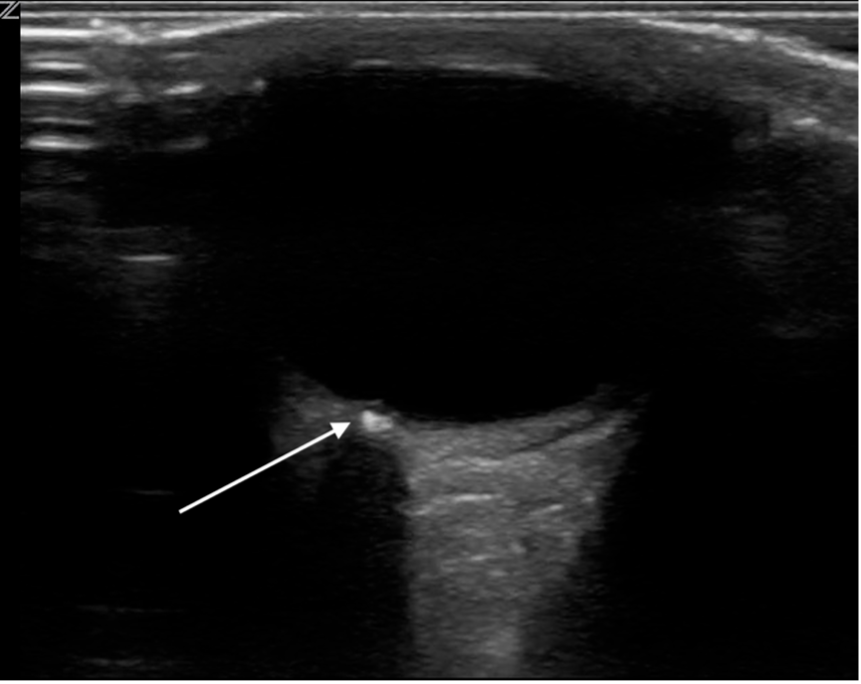

Figure 1ab: LV levels in the PLAX view (a) and A4C (b) in cardiology convention